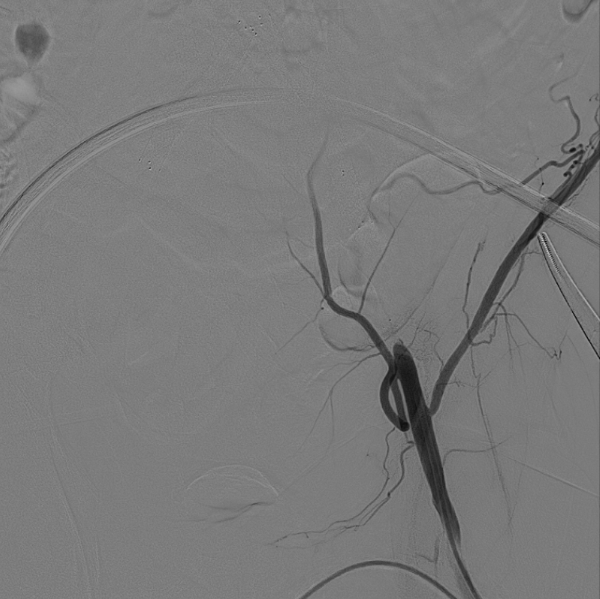

在超声引导下,成功完成双侧股总动脉穿刺。通过导管配合超滑导丝,顺利通过病变区域进入腹主动脉下段,造影明确腹主动脉下段及双侧髂动脉完全闭塞的病变范围与程度。

减容治疗

采用8F Rotarex导管对双侧髂动脉及腹主动脉下段进行减容处理。该器械对于陈旧性血栓具有良好的清除效果,且适用于支架内病变的治疗。减容治疗的主要目的在于获得理想的管腔空间,同时降低远端动脉栓塞的风险。